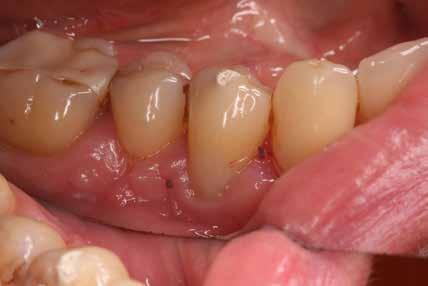

A maradó fogak gyökérreszorpciója patológiás folyamat. Az elváltozások elhelyezkedése alapján csoportosíthatjuk őket külső és belső reszorpciós folyamatokra. A külső gyökérreszorpciók egyre gyakrabban diagnosztizált formája a külső nyaki reszorpció (angolul External Cervical Resorption, ECR) [1. és 2. kép]. Az ECR egy komplex elváltozás, amely egyszerre érintheti a fog keményszöveti állományát, a parodontális szöveteket és előrehaladott esetben a pulpaszövetet is. A modern diagnosztikai eszközöknek köszönhetően egyre gyakrabban és egyre korábban kerül diagnosztizálásra ez a típusú lézió, így a kezelése is egyre inkább a mindennapi klinikum részévé válik az endodonciával foglalkozó kollégák számára. A 3 dimenziós diagnosztikai eszközök terjedésével felmerült az igény egy 3 dimenziós klasszifikációra. Patel és munkatársai 2018-ban kidolgoztak egy új klasszifikációt, amely segít az elváltozások kategorizálásában és a kezelések tervezésében [1]. A téma aktualitását jól mutatja, hogy ezzel egy időben az ESE (European Society of Endodontology) is kidolgozott egy állásfoglalást a külső nyaki reszorpciók diagnosztikájával és terápiás lehetőségeivel kapcsolatban [2].

Ötvenes éveiben járó páciensünk rutinellenőrzésre érkezett rendelőnkbe. A vizsgálat során felfigyeltünk a jobb felső metszőfogán kialakult, íny alatti elváltozásra. A röntgenfelvételen jól látható a kis méretű (Patel 1Ad) reszorpciós elváltozás [3. kép]

A külső nyaki reszorpciós elváltozások behatolási kapuja rendszerint a hámtapadás szintjében található, így a klinikus számára komoly kihívást jelenthet az elváltozás láthatóvá tétele, annak izolálása, valamint a kezelése is. Bár kutatások nagy számban foglalkoznak a reszorpciós elváltozások természetével és etiológiájával, jelenleg csak nagyon kevés tudományos evidencia érhető el a kezelésükkel kapcsolatban. Továbbá, jelenleg nincs tudományos konszenzus a restaurálásra alkalmazható anyagok tekintetében sem. Számos kérdésre kell választ találnunk a kezelésünk megtervezése közben. Elsődleges célunk, hogy a külső nyaki reszorpcióval diagnosztizált fogakat funkcióban tartsuk, megelőzzük a további keményszövet-veszteséget és helyreállítsuk az esztétikumot (kiváltképpen az anterior régióban). Nagy méretű reszorpciós kavitások esetén már felmerülhet a fog megerősítésének kérdésköre is. Mivel a restauratív anyagunkat

A megfelelő vizuális kontroll és az izolálhatóság kedvéért lebenyt alakítottunk [4. kép]. Így az abszolút izolálás már kivitelezhető volt és kofferdám izolálásban kezeltük a léziót [5. kép]. Mivel az elváltozás nem látható területen helyezkedett el, illetve a kavitás kis kiterjedését figyelembe véve kalcium-szilikát bázisú anyagot választottunk a restauráláshoz (Biodentine, Septodont) [6. kép]. Miután letelt a választott anyagunk kötési ideje (12 perc), zártuk a lebenyt [6. kép]. Páciensünk azóta is panaszmentes, kétéves kontrollon állapota rendben volt [7. és 8. kép].